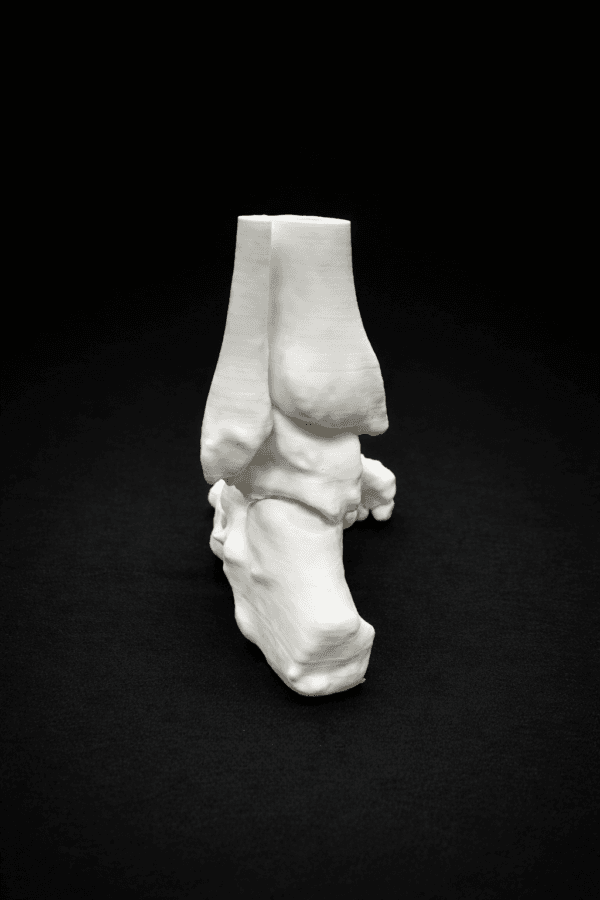

| Pathology | Pes Cavus |

| Procedure | Cole Osteotomy, Dwyer, Lateralizing Calcaneal Osteotomy, Metatarsal Dorsiflexion Osteotomy |

| Area | Midfoot |

| Modularity | Single-piece |

| Material | Opaque |

Pes Cavus – Bone Model